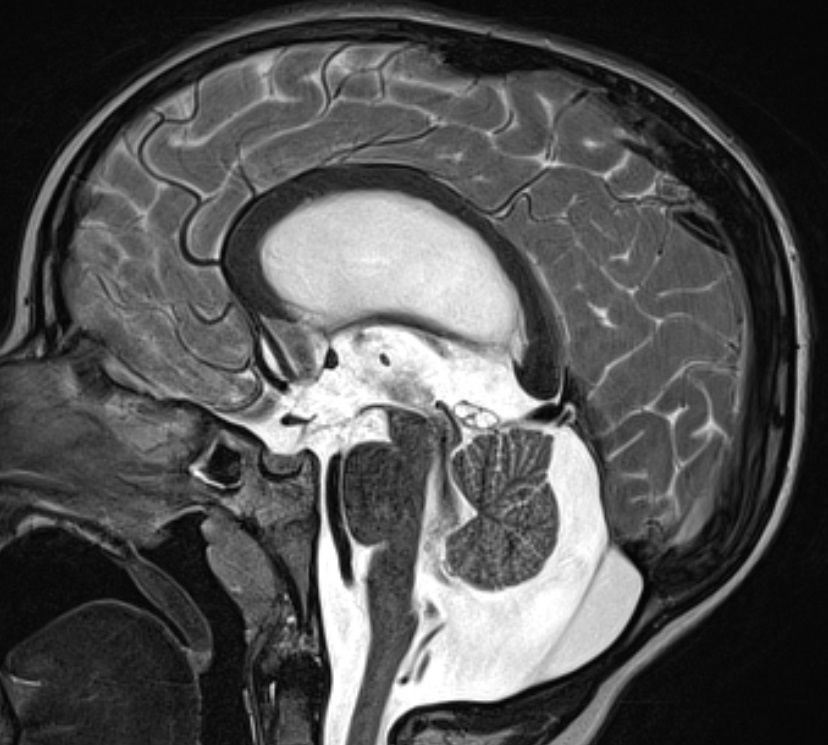

病例展示为1例6岁特发交通性脑积水患者,在计划和实施VP分流手术过程中涉及几点临床决策。

1例6岁男性患儿,有慢性头痛和语言迟缓症状,一次摔倒后撞伤头部遂行影像学检查。

脑室明显扩大。

轻度视乳头水肿伴头痛病史,经眼科检查确诊为脑积水。

交通性脑积水确诊理由:

四个脑室均扩大;

MRI对通过中脑导水管的CSF流动研究显示CSF流动通畅;

CISS/FIESTA 序列精细扫描研究未发现任何阻碍阻碍脑脊液流出的网状物。